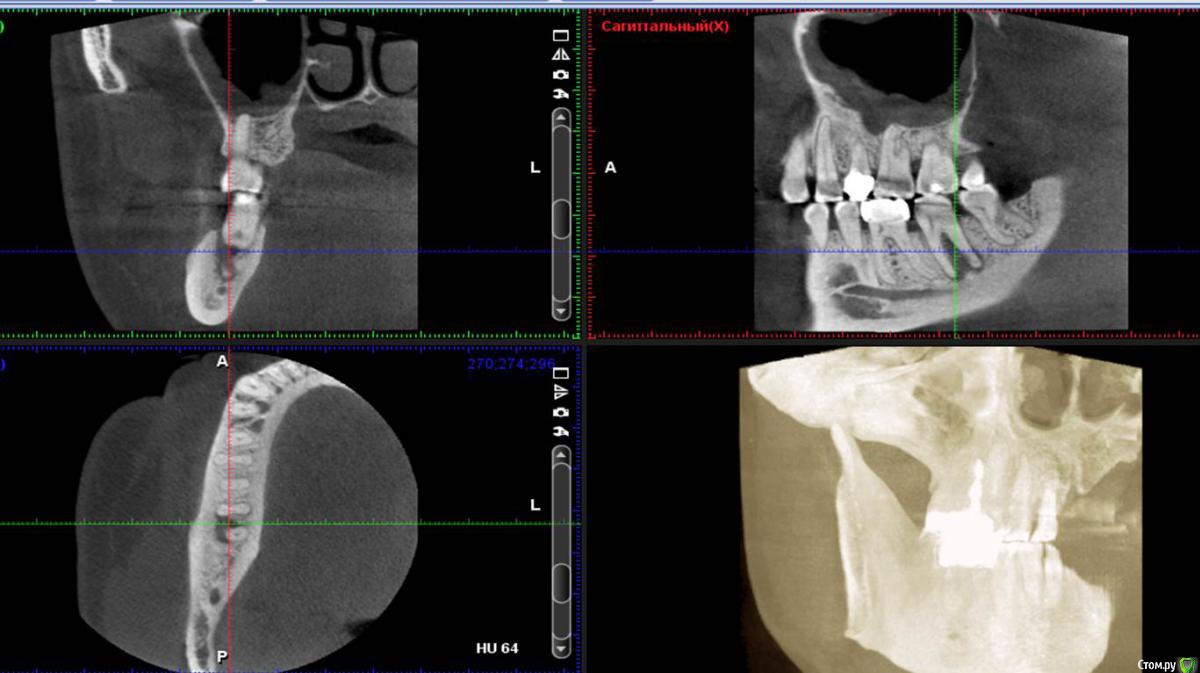

Сева северный Опубликовано 21 апреля, 2016 Поделиться Опубликовано 21 апреля, 2016 (изменено) .Хотелось бы выслушать мнение по зубу 4.6Пациент пришел по рекомендации, коллеги, из сторонней клиники. . Как бы вы поступили в данной ситуации? ( Скриншоты КТ, прилагаются) Изменено 21 апреля, 2016 пользователем Сева северный Ссылка на комментарий

Сева северный Опубликовано 21 апреля, 2016 Автор Поделиться Опубликовано 21 апреля, 2016 (изменено) Мужчина. Возраст: около 50,Жалобы. на болевые ощущения ..отсутствуют. Зуб ранее лечен, имеется старая пломба с нарушенным прилеганием, по границам- кариес. Пальпация, перкуссия безболезненна, в области бифуркации при надавливании, появляется жидкость, желтоватого цвета. При зондировании зонд погружается в межкорневое пространство примерно на 15 мм. Изменено 21 апреля, 2016 пользователем Сева северный Ссылка на комментарий

Сева северный Опубликовано 27 апреля, 2016 Автор Поделиться Опубликовано 27 апреля, 2016 (изменено) Это надо в Вк запостить, для удаляторов)Да там такого много. Вопрос удаления. конечно рассматривался... Но для имплантации, потеря зоны костной перегородки в зоне бифуркации, достаточно критична. Поэтому.. приняли решение эндосанации . (повыращивать кость), а в случае успеха обойтись без нее. Как показывает практика, большие очаги, особенно если не ступала ((((нога стоматолога , с гипохлоридом, быстро... схлопываются. Изменено 27 апреля, 2016 пользователем Сева северный 2 Ссылка на комментарий